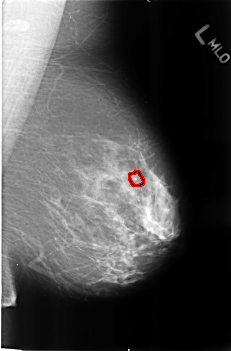

B_3247_1.LEFT_MLO

LEFT_MLO LINES 4560 PIXELS_PER_LINE 3000 BITS_PER_PIXEL 12 RESOLUTION 50 OVERLAY

FILE: B_3247_1.LEFT_MLO.OVERLAY

TOTAL_ABNORMALITIES 1

ABNORMALITY 1

LESION_TYPE CALCIFICATION TYPE LUCENT_CENTER DISTRIBUTION N/A

ASSESSMENT 2

SUBTLETY 3

PATHOLOGY BENIGN_WITHOUT_CALLBACK

TOTAL_OUTLINES 1

BOUNDARY